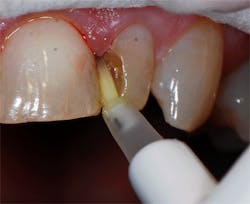

An Epitex clear matrix strip (GC America Inc.) was placed interproximally on the mesial, and the preparation was filled with G-ænial Sculpt (GC America Inc.), a compactable, universal composite, in shade A3 to build out a contact with the adjacent central incisor (figure 4). The composite was placed from the unitip and adapted with an instrument to cover the dentin and contact the Epitex strip.

Figure 4: An Epitex clear matrix strip was placed interproximally, and G-ænial Sculpt in shade A3 was placed into the preparation incrementally, shaped, and light cured for 20 seconds.

Because a significant portion of the tooth was missing on the mesial after removal of the defective composite, the restoration needed to be built up in increments. First, the contact was established and light cured with an LED curing light (The Light 405, GC America Inc.). Next, composite was added to the lingual to build the desired anatomy and light cured. Finally, the anatomy was constructed on the facial to the full contour, completing the restoration. The author recommends covering the entire facial surface with at least a thin layer of composite to place the margin between the resin and tooth structure in a nonvisible area. Should any staining occur in the future, it will help to hide any possible future color changes at the margin.